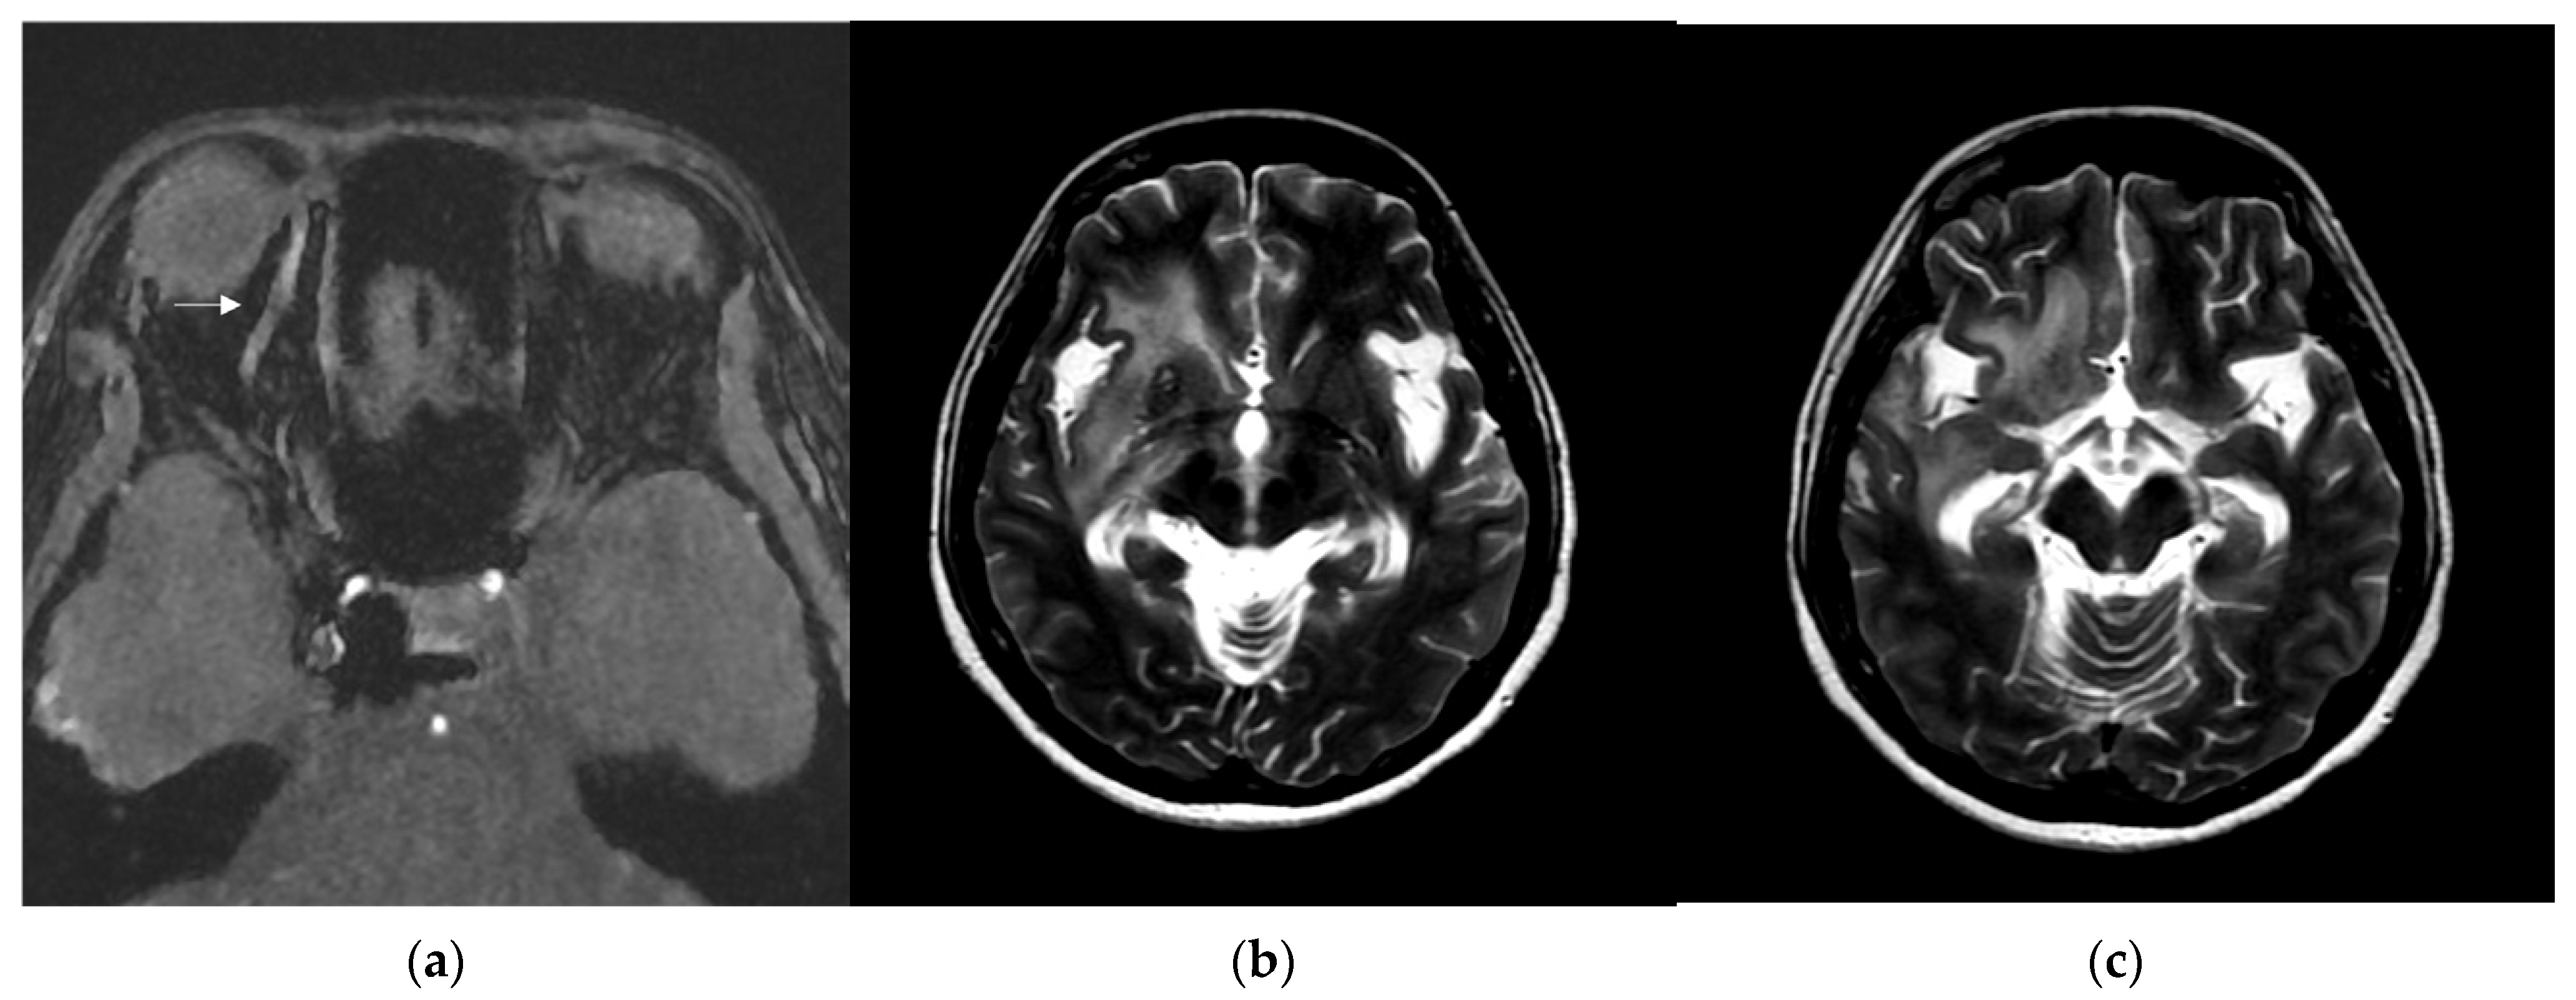

Figure 3.

(a) Brain magnetic resonance imaging (MRI) axial view, T1-weighted imaging with contrast disclosed engorgement of right superior ophthalmic vein (arrow head), and swelling of right orbital cavity (star); (b) brain MRI axial view, T2-weighted imaging show high T2 signal change in right corpus striatum; and (c) axial view of brain MRI T2-weighted imaging show enhancement at right insular lobe, right frontal inferior lobe, right medial temporal lobe, midbrain, and pons, which indicate perifocal cerebral edema.

Brain MRI was followed up 3 days after endovascular treatment, which disclosed significantly decreased engorgement of the right SOV (Figure 5a) and less perifocal edema in the right corpus striatum, midbrain, and pons (Figure 5b,c). Consequently, a conservative strategy was implemented to address residual CCF. We conducted a follow-up DSA one month after the TVE. The DSA revealed that the residual CCF had spontaneously resolved without additional cortical reflux (Figure 6a,b). The patient experienced a complete remission of ophthalmic symptoms (Figure 2c); her conscious level and the intraocular pressure of her right eye (Table 1) both had a favorable recovery.

Figure 5.

(a) Brain MRI was followed up 3 days after endovascular treatment: axial view of brain MRI T1-weighted imaging with contrast disclosed significantly decreased engorgement of the right superior ophthalmic vein (arrow head); (b,c) brain MRI axial view, T2-weighted imaging showed less perifocal edema in the right corpus striatum, midbrain, and pons comparing to the condition before endovascular treatment.